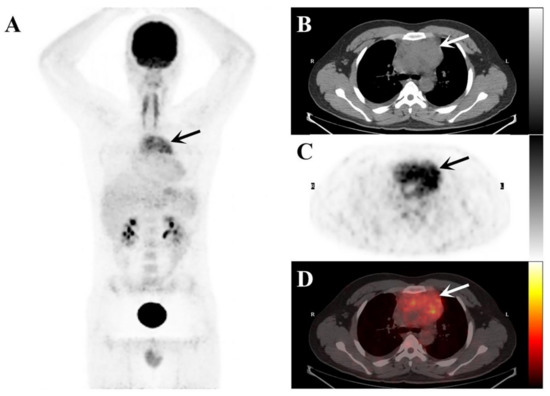

Figure 2.

The maximum intensity projection (MIP) image of the 18F-FDG PET/CT (A) demonstrates elevated 18F-FDG uptake in the mediastinal region (black arrows). The axial images ((B), plain CT; (C), PET, and (D), fusion PET/CT) demonstrate a soft tissue mass in the anterior mediastinum (arrows) surrounding the ascending aorta.

A 23-year-old man presented with a 5-day history of right-sided chest pain. The physical examination displayed no obvious abnormalities. His laboratory tests revealed increased C-reactive protein (15.36 mg/L; normal range: 0–3 mg/L) and hyperglobulinemia (40.7 mg/L; normal range: 20–40 mg/L). The chest CT (Figure 1) and 18F-PET/CT (Figure 2) were used to assess the locoregional extent and clinical stage of the disease, respectively. CT examination showed a soft tissue mass in the anterior mediastinum measuring 8.5 × 5.0 cm² approximately with unclear boundaries. The plain CT value was 40 HU, and the enhanced CT value was 87 HU. This patient was initially diagnosed with lymphoma or thymoma by experienced radiologists. Subsequently, PET/CT showed abnormally high FDG uptake (SUVmax: 8.96) in this lesion. No other abnormal 18F-FDG-avid lesion was observed.

Combined anatomical localization and functional metabolism, PET/CT is often used for disease diagnosis and staging evaluation. In this case, the soft tissue mass in the anterior mediastinum showed FDG avid, presumably because of histiocytosis and surrounding inflammation [14,15]. Primary thymic RDD resembles many diseases in appearance, FDG avidity, and distribution [16]. It has a wide range of differential diagnoses, including thymoma, lymphoma, infectious disease, metastatic disease, and histiocytosis. Therefore, RDD should also be considered in the diagnosis of the mediastinal infiltrative lesion in young patients with a higher FDG uptake.